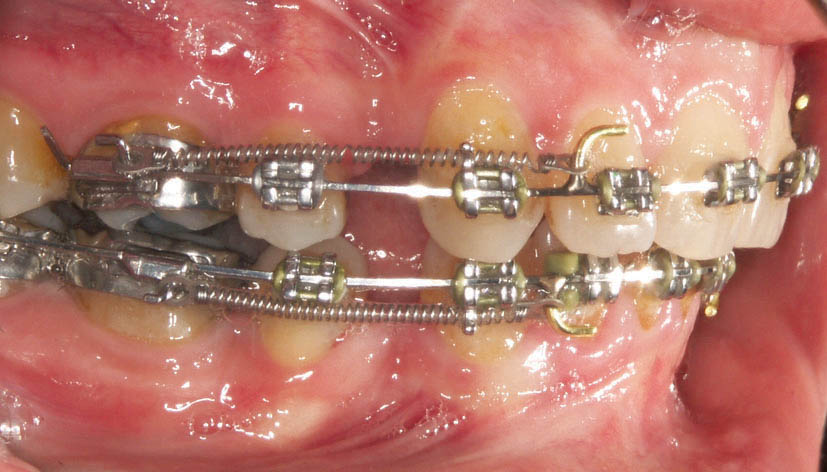

نوع باز آن به نام open coil spring برای باز کردن فضا استفاده میشود. مثلاً دندان لترال در کراس بایت است (شکل 184-1) و فضا برای قرار گیری درون قوس فکی ندارد.

شکل 184-1: وقتی فضا برای درون قوس قرارگرفتن لترال پالاتالی نداریم از فنر open نیتی استفاده میشود تا فضا باز شود.

در بیماران به روش کشیدنی با استفاده از laceback دندان كانین را به دیستال حركت میدهیم تا فضا برای لترال پالاتالی فراهم شود. حركت دیستالی كانین باعث حركت مزیالی دندان 5 و 6 میشود. اگر حركت مزیالی دندان 6 مطلوب نباشد و هم چنین پروترود شدن سانترال نیز مد نظر باشد (اصلاح میدلاین یا اضافه کردن اورجت) به جای استفاده از laceback، از فنر استفاده میكنیم تا باعث جلو آمدن سانترال و عقب رفتن کانین به طور همزمان شود (شکل 185-1). به هنگام استفاده از فنر معمولاً

bendback نمیزنیم (خم کردن سیم در انتهای تیوب مولر دوم) تا فضا سریعتر باز شود.

با گذاشتن فنر باز بین براکتهای سانترال و کانین برای لترال فضا ایجاد میشود (شکل 185-1). برای این منظور مقداری از فنر open را (30 درصد بیشتر از فاصله دو براکت) بریده و آرچوایر را از درون آن رد میکنید. بعد از جا گذاری به علت فشرده شدن باعث اعمال نیرو شده و دو دندان سانترال و کانین را از هم دور میکند. اگر bendback زده باشید، فقط کانین عقب میرود اما اگر bendback نزده باشید هم کانین عقب میرود و هم سانترال جلو میآید. در صورتی که بین دو سانترال فضا باشد ابتدا فضا بسته میشود بعد سانترالها پروترود میشوند (و بدیهی است که اگر یکطرفه فنر گذاشته باشید مقداری میدلاین به سمت دیگر حرکت میکند).

شکل 185-1: بعد از مرتب شدن تمام دندانها به غیر از لترال، فنر باز بین براکت سانترال و کانین قرار میدهیم تا فضا برای لترال ایجاد شود.